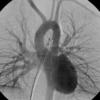

PA angio

Fig 1